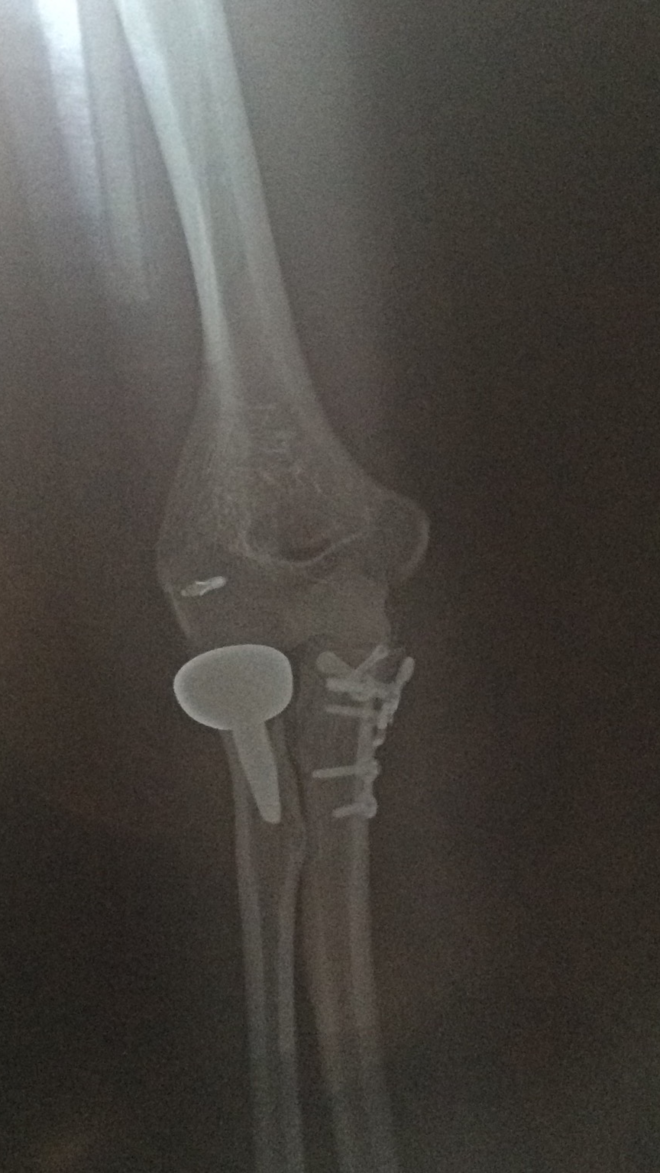

李敏彬受伤后,一开始感觉不太疼,以为并不严重。直到他回到家中左臂手肘始终不能自如活动,并且肘部逐渐肿胀起来。晚上疼痛开始愈发严重,赶紧去了医院。结果出乎意料,李敏彬手肘被诊断为粉碎性骨折,需要紧急做手术。

“完全没有想到会伤得这么重,医生说就是‘放屁扭腰,寸劲儿了’。”之后数月时间,李敏彬接受3次手术,植入部分假体,再加上又数个月的康复才终于痊愈。